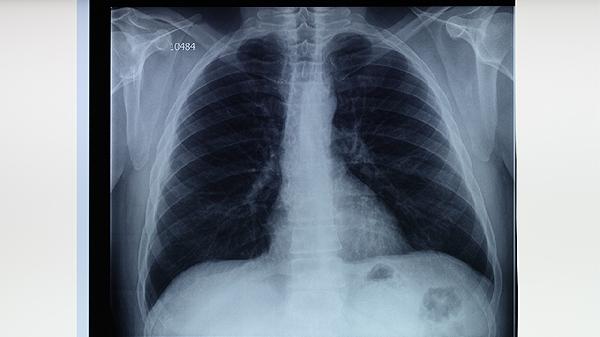

免疫功能低下者可能出现肺内结核球增大或播散,导致稽留高热。胸部CT检查可明确病灶范围,严重者需考虑外科手术切除。联合使用注射用硫酸链霉素等强化治疗,并补充维生素B6片预防神经毒性。